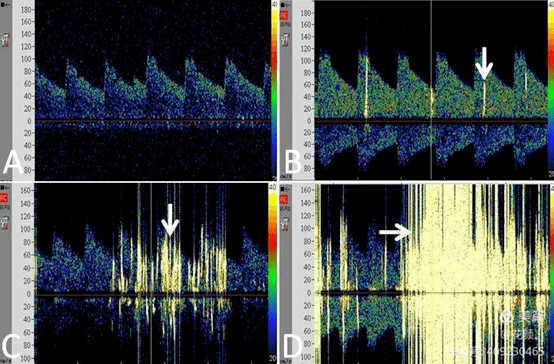

沿肺动脉进入肺循环,不会进入体循环动脉里,因此tcd无频谱形态变化